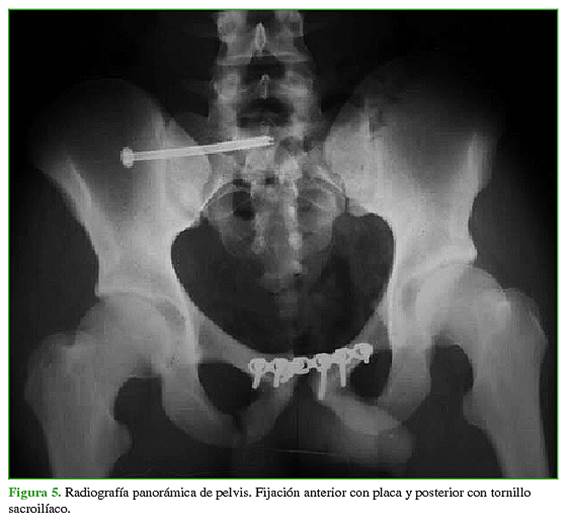

Los tipos de fijación analizados se dividieron en dos grupos. El primer grupo incluyó a los pacientes operados con fijación anterior con placa mediante un abordaje de Pfannenstiel y percutáneo sacroilíaco. Al segundo grupo lo conformaron los pacientes operados únicamente con fijación anterior con placa por medio de un abordaje tipo Pfannenstiel (sin fijación posterior), más los operados con fijación externa anterior y percutánea sacroilíaca. La división en grupos se realizó de esa manera para comparar el tratamiento más aceptado en la actualidad y recomendado en la bibliografía (fijación anterior con placa y posterior percutánea), con el resto de los tratamientos realizados. El tratamiento para cada paciente se seleccionó según las características de cada uno de ellos, sus enfermedades y lesiones asociadas, y en conjunto con los demás servicios tratantes. Además, los primeros pacientes de la serie habían sido tratados solo con fijación anterior, en los últimos años de la serie, se agregó la fijación posterior percutánea. La fijación anterior se realizó, en todos los casos, con una placa de reconstrucción o una placa DCP de 3,5 mm, según la disponibilidad. La mayoría de los pacientes fueron operados con placas de reconstrucción de 3,5 mm y dos, con placas DCP 3,5 mm. Los tornillos sacroilíacos utilizados fueron de 6,5 mm y 7 mm.

A cinco pacientes (21,73%) se les realizó únicamente fijación anterior con un abordaje tipo Pfannenstiel, 13 (56,52%) fueron operados mediante fijación anterior y percutánea sacroilíaca (Figuras 5-7) y cinco (21,73%), mediante fijación externa anterior y percutánea sacroilíaca. La reducción posoperatoria fue <1 cm en 16 pacientes (69,57%). Cinco (21,73%) sufrieron una infección del sitio quirúrgico.